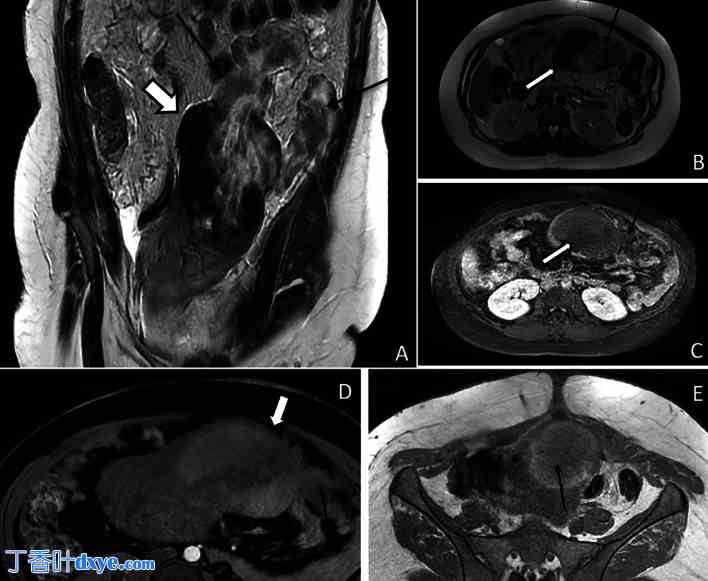

术后第4天进行的MRI检查证实存在侧蒂浆膜下子宫底肌瘤,符合FIGO 6型。该肌瘤在T2加权像上呈异质性信号,在T1加权像上呈高信号,符合出血表现。肿块内未见对比增强。这些表现符合肌瘤的红色变性。

此外,肌瘤左侧表面可见4厘米的缺损,腹腔内可见异质性肌瘤碎片(图3)。

图 3.

MRI 图像。(A) 冠状位 T2 加权像显示腹膜下肌瘤(粗箭头),其上有一个 4 cm 的穿孔,异质性坏死组织(细箭头)渗漏至腹腔。(B) 轴位 T2 加权像显示浆膜下梗死性平滑肌瘤(粗箭头),异质性坏死组织从其左上缘发出(细箭头)。(C) 轴位 T1 加权像(脂肪抑制和对比剂增强)显示肌瘤无强化(粗箭头),提示红色变性,同时可见组织从穿孔处渗出(小箭头)。 (D)轴位脂肪抑制T1加权像显示肌瘤(粗箭头)弥漫性高至中高信号强度,其左上缘可见散在组织(细箭头),提示红色变性。(E)轴位T1加权像显示梗死肌瘤(箭头)弥漫性高至中高信号强度。